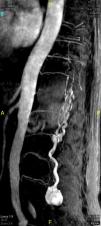

En la resonancia magnética nuclear (RM) lumbar se encontró una lesión expansiva intradural en el cono medular, hipervascularizada y con aporte arterial arrosariado4, desde D10, que ocupaba casi la totalidad del canal raquídeo hasta la altura de L5. Se confirmó por arteriografía espinal un tumor hipervascularizado irrigado por una arteria de moderado tamaño y una gran y tortuosa arteria espinal anterior no candidata a embolización5,6 (figs. 1-3).

Posteriormente, permaneció asintomática hasta que al cuarto año de seguimiento la paciente recurrió con un dolor lumbociático en la pierna derecha, con una RM lumbosacra que mostró progresión tumoral. Debido al riesgo neurológico de una nueva cirugía, se decidió embolizar la lesión través del pedículo derecho de L4, con lo que se consiguió una gran desvascularización de la lesión. Tras el procedimiento, la paciente permaneció asintomática hasta que al tercer mes reapareció la clínica, momento en que se realizó otra RM que mostró nueva progresión de la lesión, por lo que se decidió una nueva cirugía, en la que se consiguió una resección muy parcial debido a la gran adherencia tumoral y cicatricial a las raíces de L5 y S1, que obligaron a detener la cirugía por riesgo de secuelas neurológicas importantes.